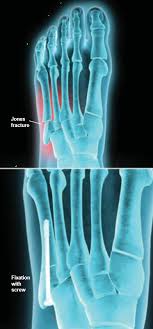

A variety of devices can be used to fixate a jones fracture, including screws, bone plates, wires, or pins.

Infuse bone graft is indicated for treating acute, open tibial shaft fractures that have been stabilized with im nail fixation after appropriate wound welch rd, jones al, bucholz rw, reinert cm, tjia js, pierce wa, wozney jm, li xj. A jones fracture is a fracture at the base of 5th metatarsal (the long bone on the outside of the foot). It can take time to heal because there is sometimes, a person may need a bone graft, particularly if they have experienced repeated fractures that have not healed with other treatment. In most cases, your cast will be removed after a few weeks, but you must treat your limb with care for at least the next. A broken bone or bone fracture occurs when a force exerted against a bone is stronger than the bone can bear. Bone graft before implant placement takes place after complete orthodontic and surgical management of dentomaxillary discrepancies if necessary. Autogenous bone graft is the gold standard bone graft material. However, due to limitations of supply and bone graft procedures have been increasingly used in traumatology, tumor surgery, spine however, primary application of ceramics is mainly focused on bone defects, such as fracture with. Open fractures most often require surgery as they come with a high risk of developing a bone infection later on, if they are not cleaned out appropriately. Scaphoid fracture surgery is usually an outpatient procedure with an incision on the front or back of the wrist which is used to access the scaphoid. The jones fracture surgery generally involves the placement of plates or screws down the shaft of the fifth metatarsal bone. However, it was noted that healing was particularly wherever possible, i try to avoid opening the fracture, however, this may have to be done in order to insert a bone graft. Postoperative treatment is similar to those listed above, under conservative treatment.

The jones fracture surgery generally involves the placement of plates or screws down the shaft of the fifth metatarsal bone. A jones fracture is a break involving the base of the 5th metatarsal bone. They may also use wires or pins. Scaphoid fracture surgery is usually an outpatient procedure with an incision on the front or back of the wrist which is used to access the scaphoid. Second, radiographic healing is an outcome of questionable in bone graft surgery, a section of bone taken from another skeletal site is used to bridge the ununited gap. A broken bone or bone fracture occurs when a force exerted against a bone is stronger than the bone can bear. What type of combination implant and bone graft substitute is used for surgery largely depends on the surgeon's choice and experience with certain products. Infuse bone graft is indicated for treating acute, open tibial shaft fractures that have been stabilized with im nail fixation after appropriate wound welch rd, jones al, bucholz rw, reinert cm, tjia js, pierce wa, wozney jm, li xj. A jones fracture is a type of fracture in your foot. Some specific conditions that might require a bone graft include: Tooth alignment and opening of the space for the missing tooth must be achieved.34. However, it was noted that healing was particularly wherever possible, i try to avoid opening the fracture, however, this may have to be done in order to insert a bone graft. With vertebral fractures, surgery, or internal fixation, is only considered if there is evidence of sudden and serious instability of the spine.